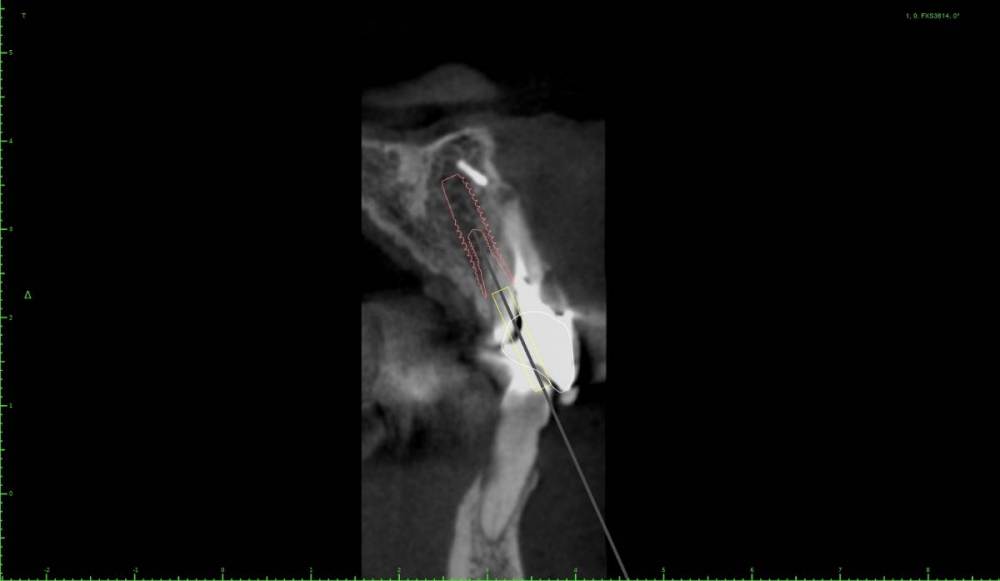

Женька Опубликовано 8 ноября, 2021 Автор Поделиться Опубликовано 8 ноября, 2021 @Irouil можно вот так ангулировать. К бломбе близко конечно. Стоит ли бояться резцового канала и его содержимого? Ссылка на комментарий

Irouil Опубликовано 8 ноября, 2021 Поделиться Опубликовано 8 ноября, 2021 Либо не трогайте, либо уничтожьте) При такой ангуляции учитывайте два фактора 1 - мнение ортопеда 2 - срезы аксиальной проекции (полагаю, там не так много ткани, как это кажется на сагитальном срезе) Ссылка на комментарий

Карен Аванесов Опубликовано 8 ноября, 2021 Поделиться Опубликовано 8 ноября, 2021 48 минут назад, Женька сказал: @Irouil можно вот так ангулировать. К бломбе близко конечно. Стоит ли бояться резцового канала и его содержимого? Не надо ничего боятся, но надо иметь 12 и 14 мм, лучше длиннее если будут такие условия и если 4мм диаметр то остановиться на фрезе 3.6 тогда будет торк, учитывая что у дяди во рту помойка, антибиотики дней на 7 и полоскания хг на 2 мес 1 1 Ссылка на комментарий